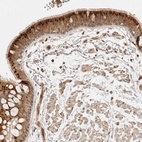

Immunohistochemical staining of human bronchus shows strong cytoplasmic positivity in respiratory epithelial cells.